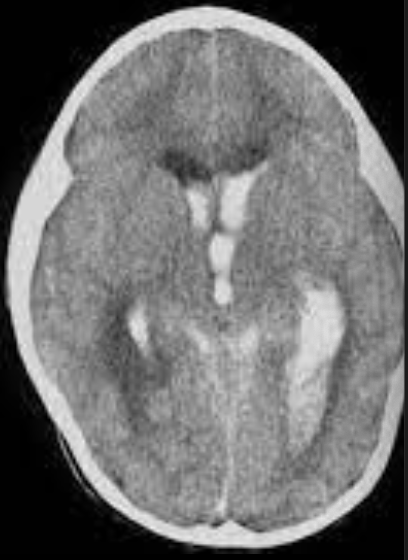

EVC hemorragico

Hipertensivo